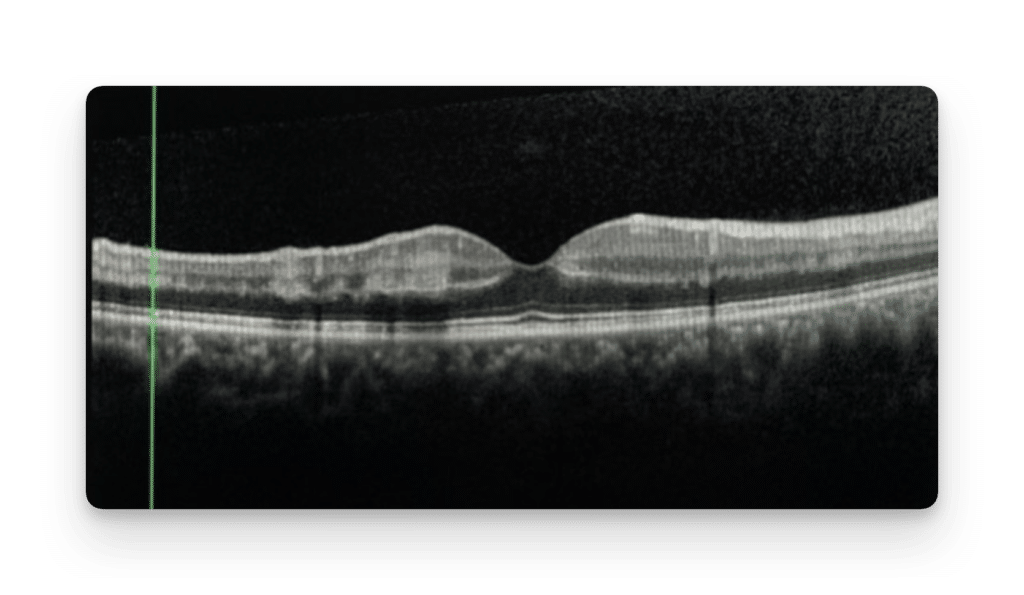

Optical coherence tomography (OCT) scans of the macula showed hyperreflective bands at the level of the inner nuclear layer consistent with paracentral acute middle maculopathy (PAMM) lesions (Figure 2). OCT scans corresponding to the dark, geographic retinal lesions showed outer retinal attenuation with hyporeflective changes at the ellipsoid zone (Figure 3). No retinal vascular occlusions or delayed circulation times were detected on wide-field fluorescein angiography (FA). Observation was recommended.

Multimodal imaging can differentiate DWP from similar appearing lesions, such as the foveal depression sign. The foveal depression sign indicates prior retinal infarction and manifests as OCT retinal thinning, whereas the DWP lesions are characterized by hyporeflective changes of the ellipsoid zone.